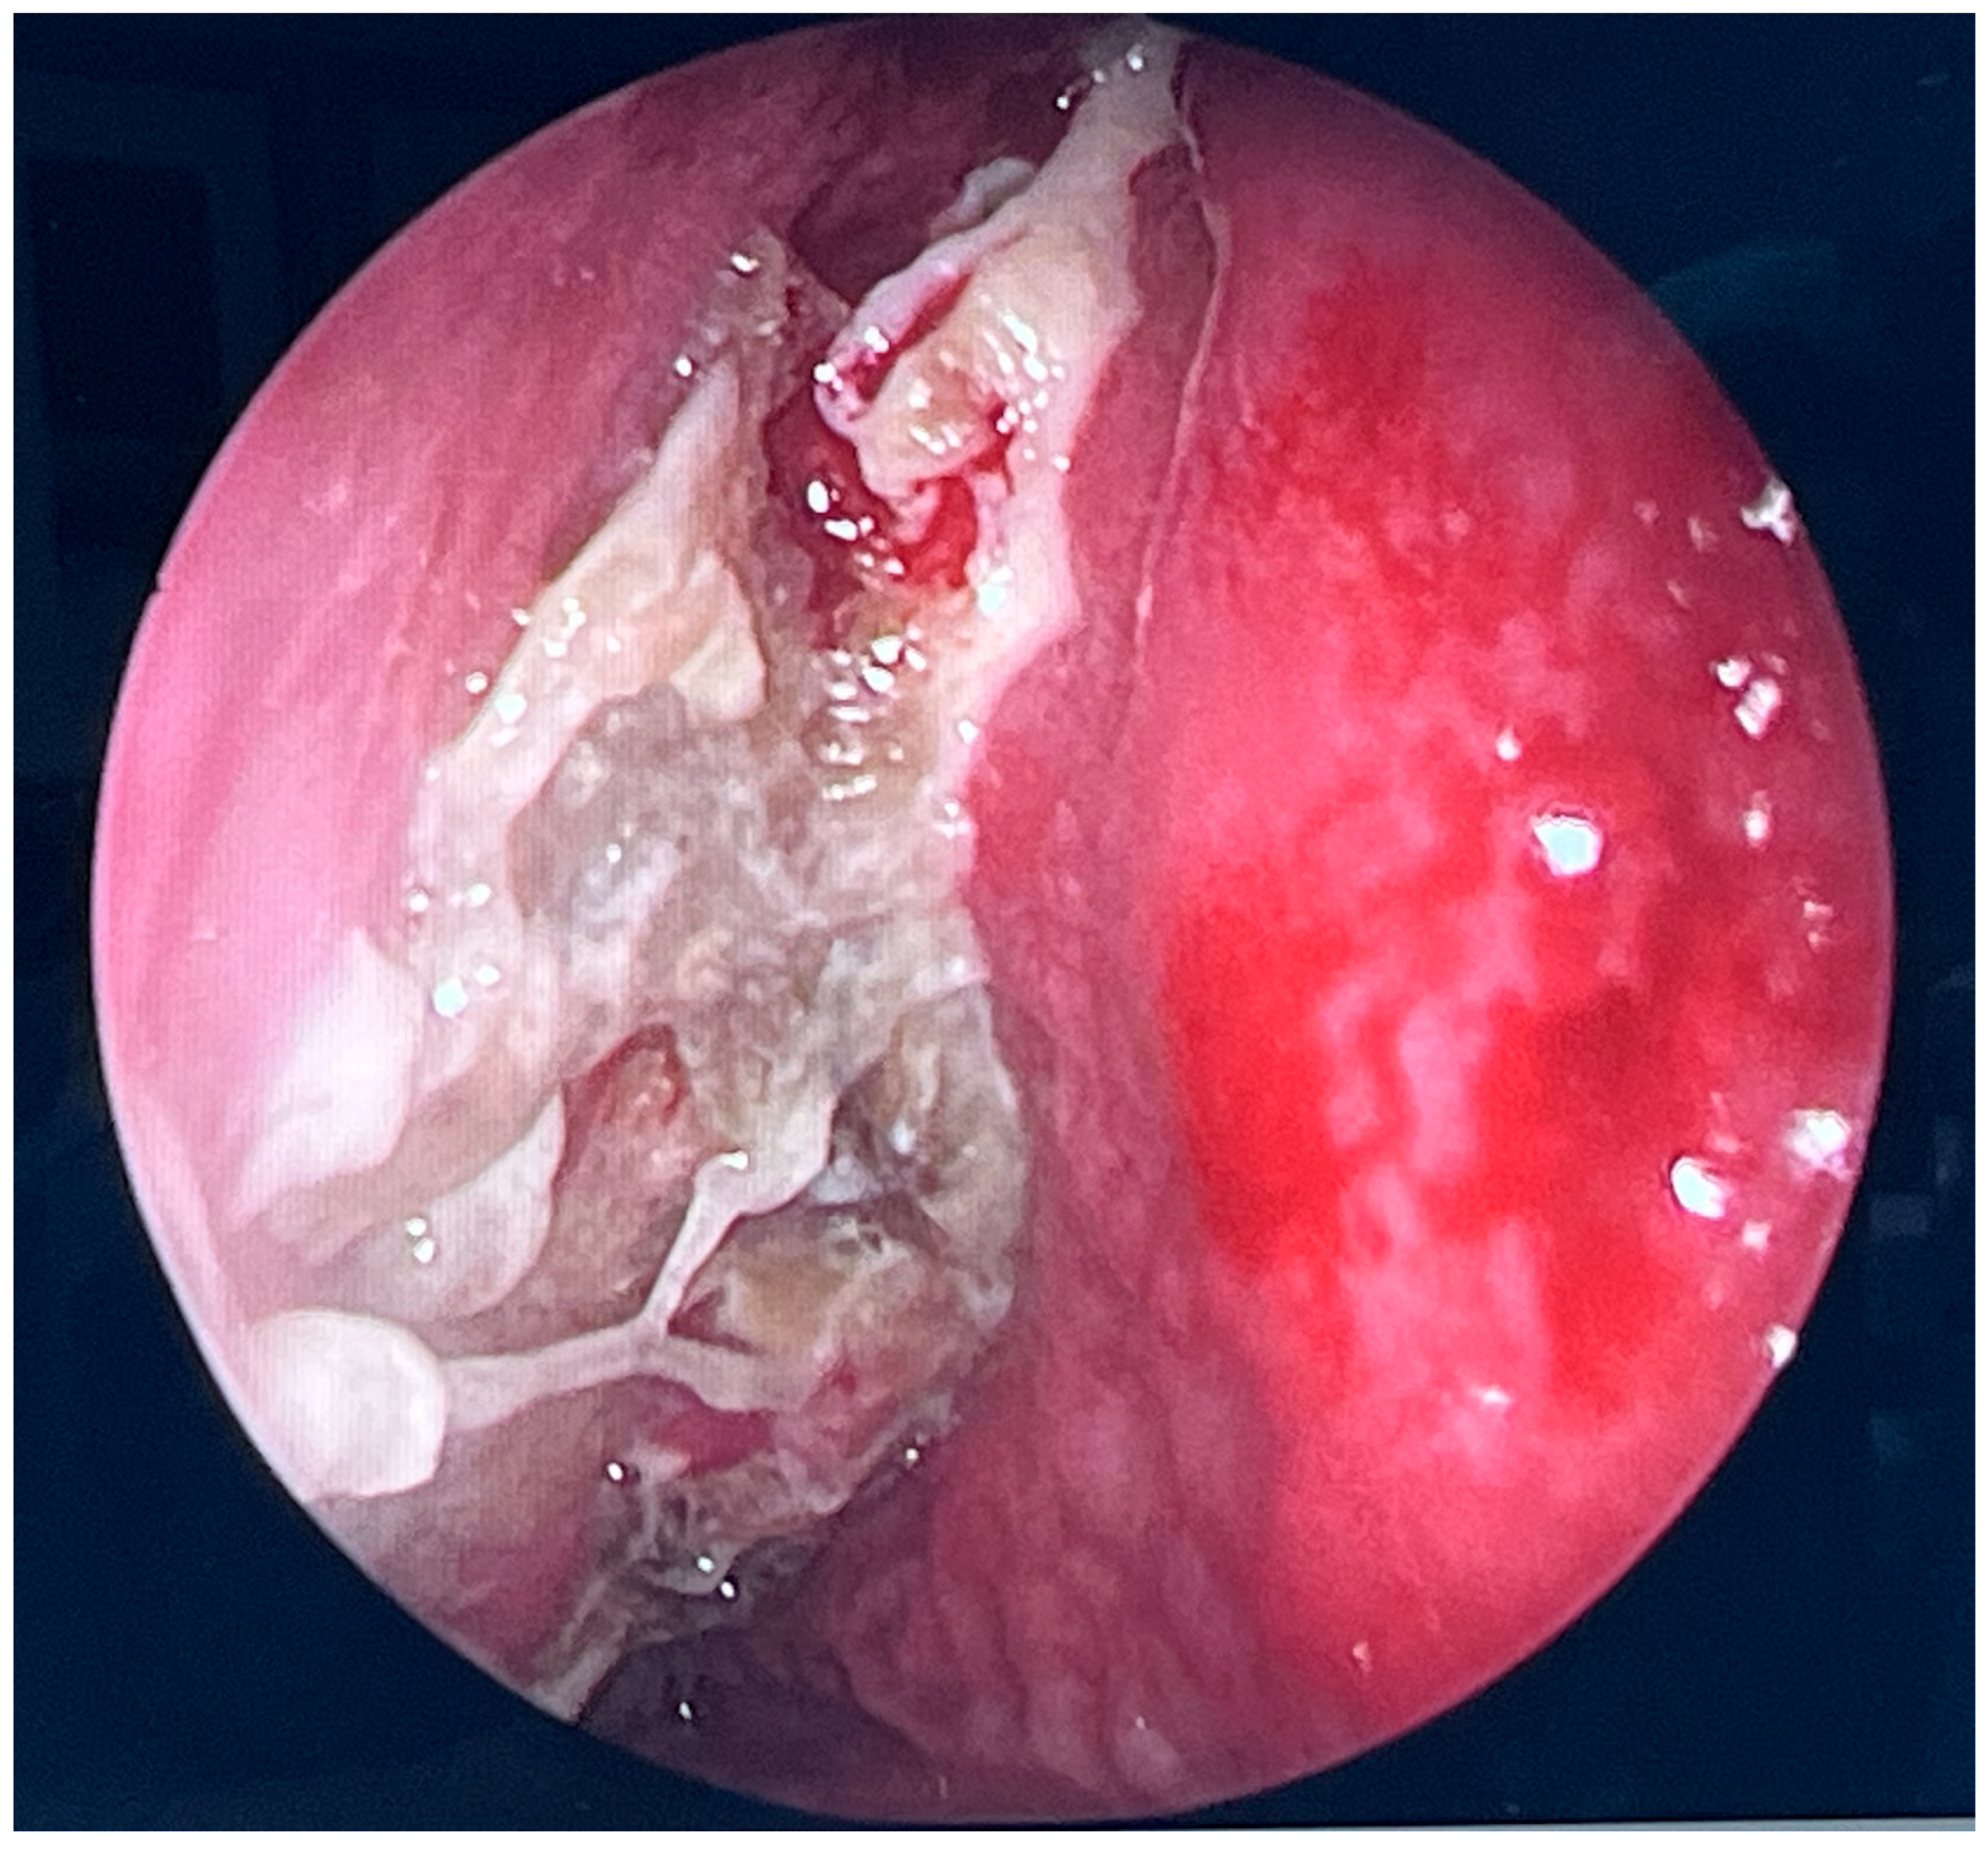

Endoscopic evaluation revealed a pronounced left-sided deviation of the nasal septum, consistent with a severe post-traumatic deformity. The right nasal cavity was completely filled with pathological tissue displaying fungal morphology. The surrounding mucosa appeared markedly inflamed and edematous, suggesting advanced fungal-inflammatory involvement.

Figure 3. Endoscopic surgery: intraoperative view showing nasal cavity filled with fungal masses.